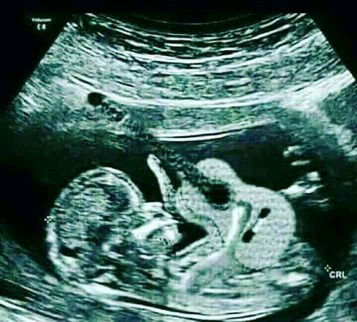

Mau tanya, kalo perut sakit saat hamil kenapa yaa?bahaya juga gak untuk kesehatan bayi ku?